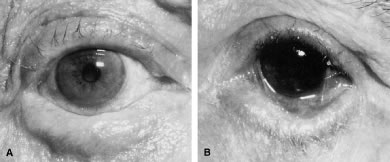

Ectropion and entropion share similar anatomic features. The most common predisposing anatomic factors for lower lid malpositions are horizontal eyelid laxity and weakness or defects of the lower lid retractors. The general weakness of the eyelid is caused by a weakness of the medial and lateral canthal tendons, permitting horizontal eyelid laxity.4 As such, it is best to consider lower eyelid laxity as resulting from laxity of the tarsoligamentous sling or support for the eyelid. The anatomic weakness can be demonstrated by the snap test. Downward retraction is exerted on the lower lid, pulling it away from the globe. On relapse, the lower lid should snap back against the globe spontaneously. Failure of the eyelid to snap back against the globe with a single blink indicates excessive laxity of the tarsoligamentous sling.

The lower eyelid retractors may be weakened or may actually become disinserted from the inferior tarsal border. Weakness or defect of the lower eyelid retractors creates in an instability of the inferior tarsal border that is manifested clinically as ectropion or entropion.

In addition, enophthalmos is associated with both ectropion and entropion. However, the role of enophthalmos as a pathophysiologic feature of lower eyelid malpositions has been grossly overstated.8,9 Enophthalmos may secondarily reduce tarsal stability by exaggerating horizontal lid laxity. It reduces the tension exerted on the eyelids by retraction of the globe and soft tissues. The normal arc or outward bowing of the eyelids is minimized with the enophthalmic globe, and eyelid tension is reduced. Retrobulbar injections stabilize eyelid malpositions by reducing horizontal eyelid laxity. Volume introduced in the retrobulbar area re-establishes the normal outward arch, or bowing, of the eyelid.

The development of ectropion and entropion is a reflection of the relationship between the anterior and the posterior lamellae. The eyelid position is maintained by an appropriate balance of the anterior and posterior lamellae. If tractional forces are unbalanced, eyelid malpositions may manifest as ectropion, entropion, or eyelid retraction. If traction is produced by the anterior lamella, either by chronic cicatricial changes or mechanical aberrations, the eyelid margin is everted away from the globe. This most commonly results from mild solar-induced changes or following surgical procedures or trauma of the eyelid, which produce a shortening or scarring of the skin and underlying orbicularis muscle.

Involutional entropion is more complex because of the multitude of factors producing this abnormality. The tarsal instability of entropic lids is due to horizontal eyelid laxity and loss of support of the lower eyelid retractors.10 The orbicularis muscle dynamics also assume a prominent pathophysiologic role in the production of entropion. In entropic eyelids, the preseptal orbicularis muscle overrides the pretarsal orbicularis muscle, which rolls the superior border of the tarsus internally. This is differentiated from spastic entropion, which is theoretically due to a spasm of Riolan's muscle. However, the primary differentiating feature of spastic entropion is a specific precipitating etiologic factor, such as recent eye surgery, eyelid edema, or ocular inflammation with secondary eyelid edema. An appreciation of the multiple etiologic causes of entropion has resulted in the evolution of combined approaches to correcting the various anatomic abnormalities and stabilizing the tarsus and orbicularis muscle.11–14